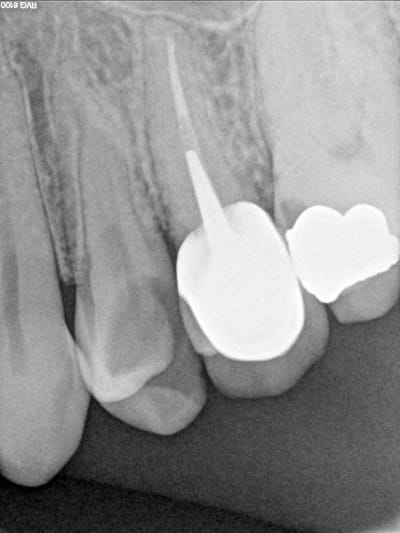

Ma consoeur : Vue 2 fois , 1 ère séance parlotte , 2 ème séance , devis et détartrage : une devis de 875 € quand même mais surtout , une chance sur 2 que ça se transforme en implant : vous comprenez , je ne suis pas sûre de pouvoir la conserver ( ça te fait marrer Chicot , moi aussi ! ) ....et toujours pas de soin de cette dent .

ç est que lorsque tu vois la radio ,eh bien tu agis de suite et tu causes après . surtout que ç est un cas facile , il n'y a besoin de microscope pour trouver la pulpe :-)

Pas compliqué faut commencer le taf et après on discute. Après avec la carie sur la 6 et la couronne sur la 5 ça commence à faire beaucoup. D’ailleurs casa elle date de quand cette couronne ?

Moi je dis, le responsable de tout ce merdier est celui qui a fait cette couronne de débutant sur la 25!

Grave... Comment peut-on laisser faire ça?! ;-)

Franchement, il aurait voulu nuire au patient qu'il ne s'y serait pris autrement...